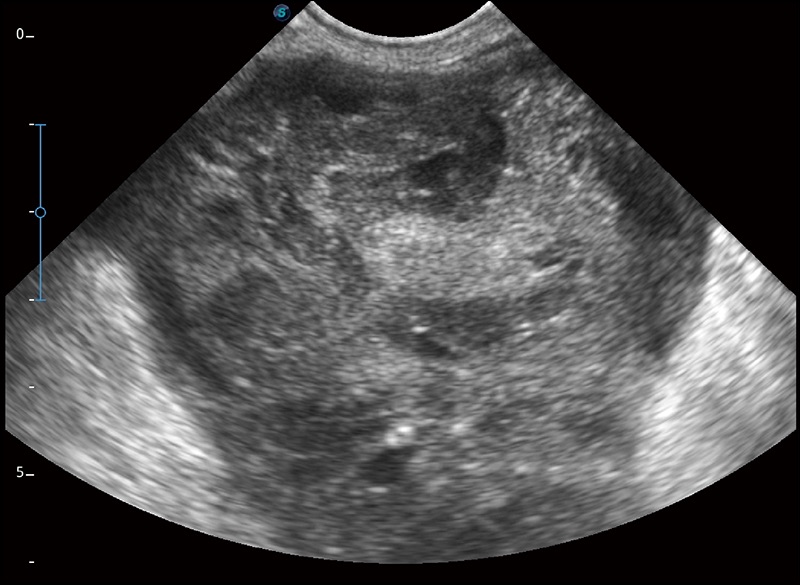

任意波束合成技术

在不牺牲时间分辨率的情况下提供出色的图像